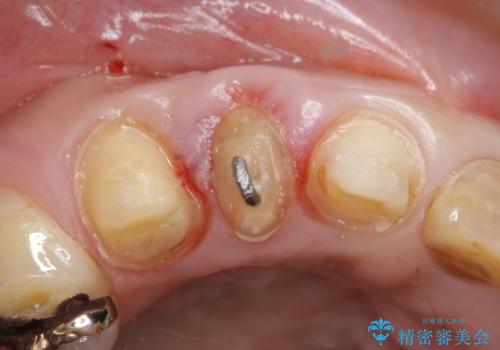

診査の結果右上2は歯根が破折しており、それが原因で骨及び歯肉の吸収が起きていました。

このまま右上2の抜歯を行うとさらに歯茎が下がる恐れがあったため、歯の挺出によって骨レベルを回復した上で抜歯し、歯槽堤保存術(抜歯窩に人工骨を填入する手術)を行いました。

その後ブリッジによる補綴を行うことで、自然な見た目を再現することができました。